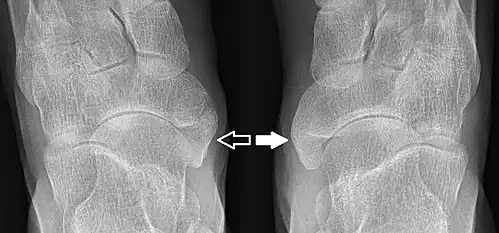

Radiographie du pied montrant un os naviculaire accessoire

Un os naviculaire accessoire est un os accessoire du pied qui se développe parfois anormalement devant la cheville vers l'intérieur du pied. Cet os peut être présent dans environ 2 à 14 % de la population générale et est généralement asymptomatique[1],[2],[3]. Lorsqu'il est symptomatique, une intervention chirurgicale peut être nécessaire.

Les radiographies sont généralement commandées pour confirmer le diagnostic. S'il y a une douleur ou une inflammation en cours, une IRM ou d'autres tests d'imagerie avancés peuvent être utilisés pour évaluer davantage la condition.

Images radiologiques